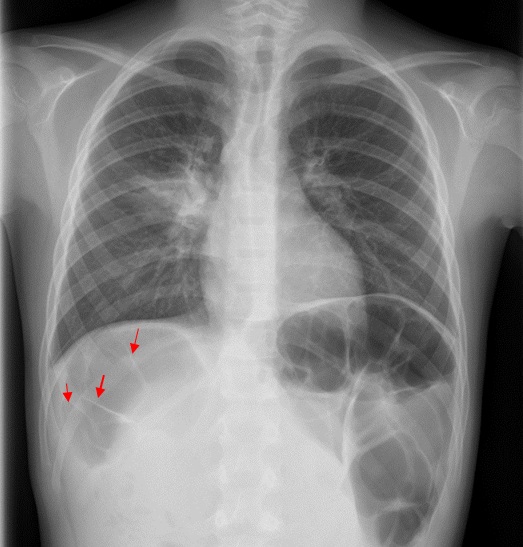

Niño de 9 años que acude a Urgencias por fiebre de hasta 38,9 °C de 72 horas de evolución asociada a tos productiva y mucosidad nasal. En la auscultación pulmonar se aprecian crepitantes en el campo superior derecho. El resto de la exploración física es normal. Se realiza radiografía de tórax posteroanterior, única proyección, que evidencia un aumento de la densidad en el campo pulmonar superior derecho, pero hay algo más (Figura 1).